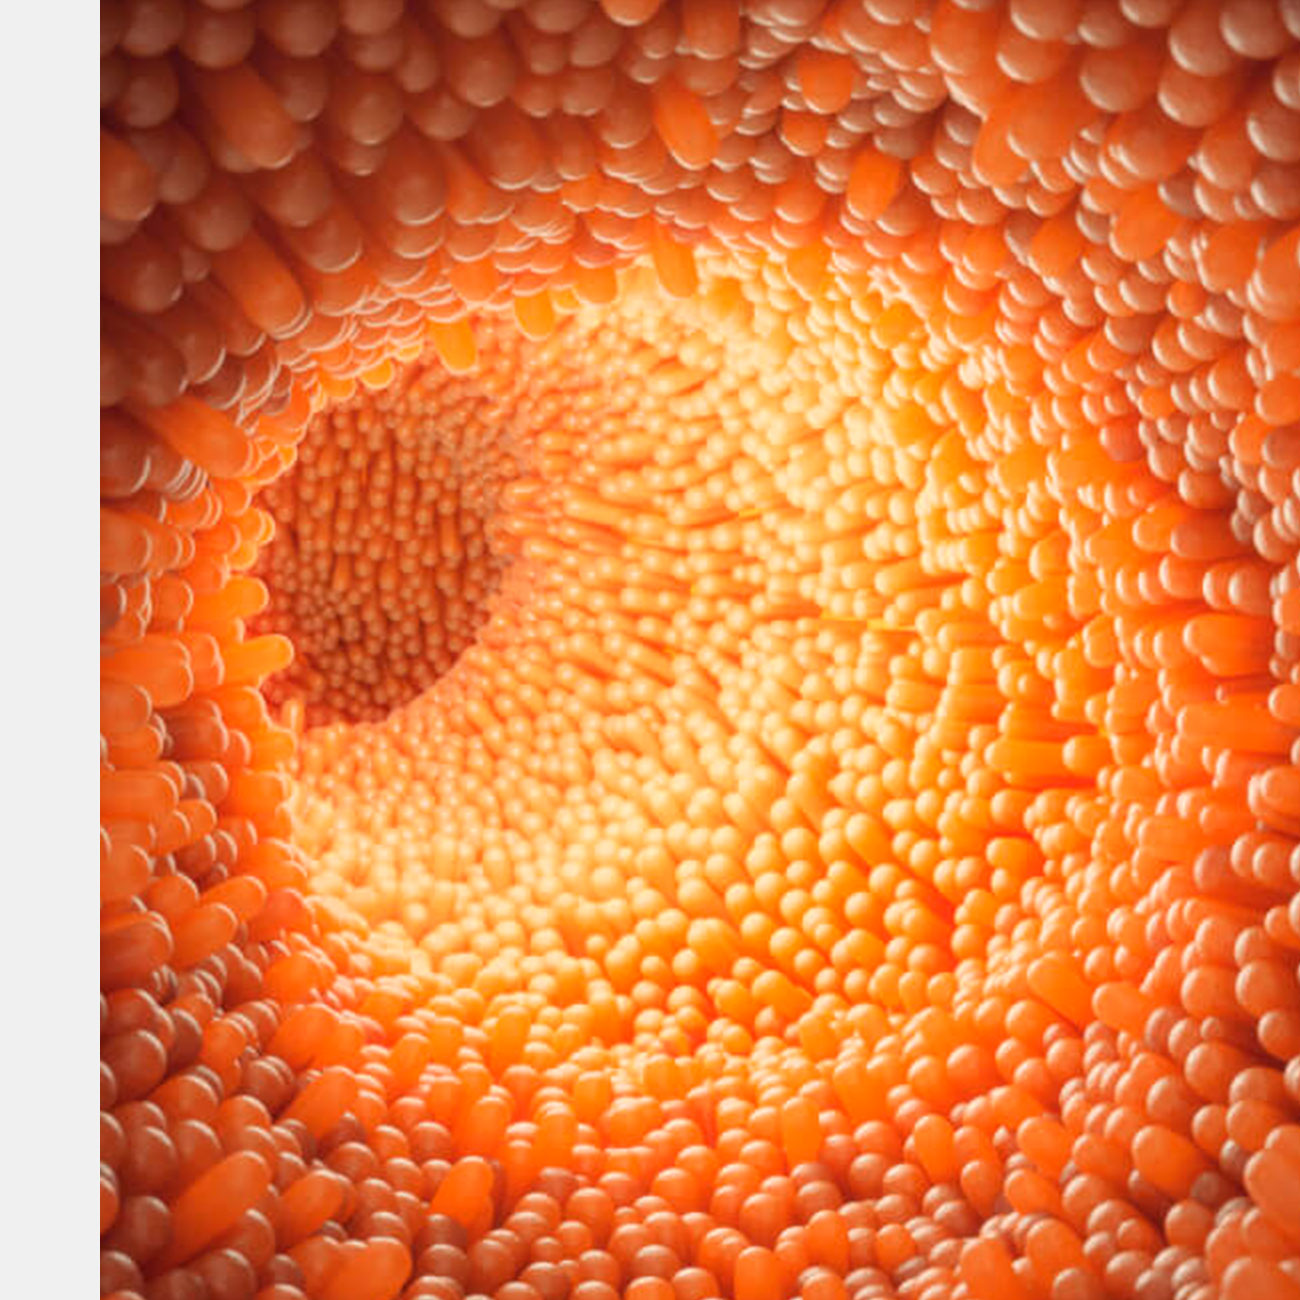

Ученые из Калифорнийского университета в Сан-Франциско (UCSF) впервые успешно отредактировали геном бактерий, которые находятся в микробиоме кишечника живых мышей.